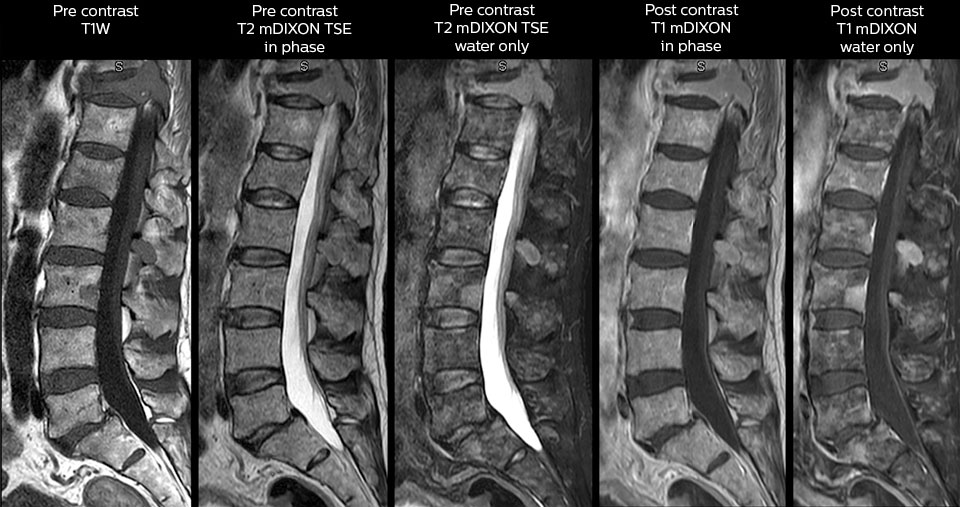

“Nous utilisons beaucoup le mDIXON TSE dans notre imagerie du rachis en service d’urgences”, déclare le Dr Karis. “Ce qui est particulièrement appréciable, c’est sa fiabilité par rapport au type de susceptibilité des problèmes pouvant survenir avec des images spectrales classiques saturées en graisse ; ces problèmes sont essentiellement éliminés grâce à la technique mDIXON. C’est vraiment un avantage de disposer de l’imagerie sans graisse nécessaire à la technique mDIXON dans notre service d’urgences.”

“Pour les examens de routine sans contraste du rachis cervical et thoracique, par exemple, nous réalisons une séquence mDIXON T2 TSE qui produit deux sorties : les images pondérées en T2 avec graisse et eau, et les images sagittales pondérées en T2 avec eau uniquement. Ensuite, nous réalisons également un examen échographique du gradient axial.”

Examen de routine du rachis cervical

Ce patient s’est présenté avec des maux de tête aggravés par la flexion du cou, et on constate une malformation de Chiari de type I avec des amygdales cérébelleuses basses ainsi qu’un changement thrombolytique cervical dégénératif.